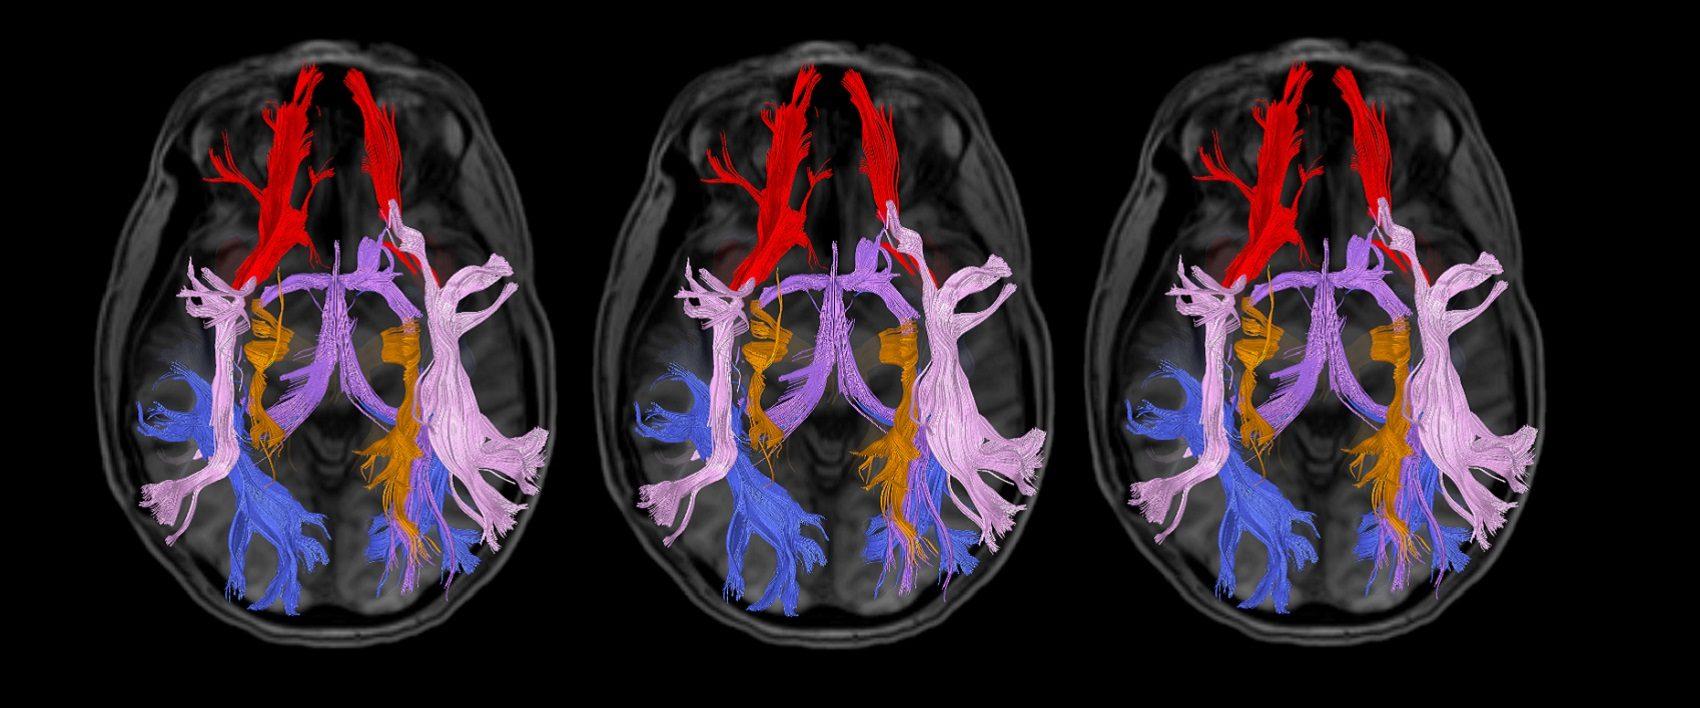

Pesquisa utiliza métodos de neuroimagem para investigar a relação entre o sistema cerebral de recompensa e o comportamento alimentar de...